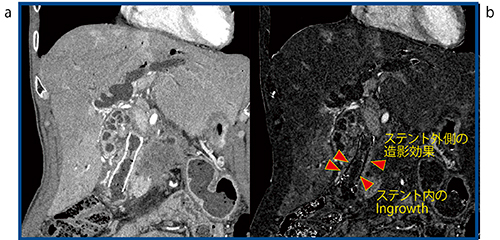

症例6は,81歳,男性の膵がんである(図6)。本症例は前医がステントを留置しているが,Aquilion Precisionではブルーミングアーチファクトがなく,ingrowthした腫瘍が造影されている(図6 a)。SURESubtractionを行うと,ステント外側の造影効果やステント内のingrowthが高精細に描出されており,診断に有用と考えられる(図6 b◀)。

図6 症例6:膵がん(Aquilion Precision)

a:造影CT画像 b:SURESubtraction